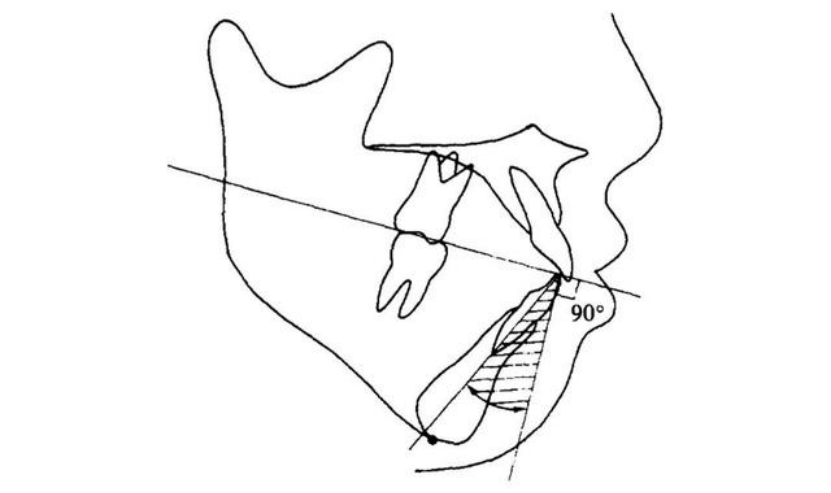

Jacobson研究认为:女性Wits值为0,男性Wits值为-1。当Wits值过大时,表示Ⅱ类骨性错牙合关系;当Wits值过小时,表示Ⅲ类骨性错牙合关系。Tweed分析法也被称作Tweed三角分析法,主要测量由眼耳平面、下颌平面和下中切牙长轴所组的三角形构成。由于其定点简单、直观、易测,目前为临床医生做常规头影测量分析时,特别是判断拔牙及预后侧貌评估中广为应用的一种方法。

a.眶耳平面-下颌平面角:眶耳平面与下颌平面的交角,以下颌下缘的切线作为下颌平面。b.下颌中切牙-眶耳平面角:下颌中切牙长轴与下颌平面的交角。c.下颌中切牙-下颌平面角:下颌中切牙长轴与下颌平面交角。在Tweed分析法中,不论错牙合畸形的部位在哪,均以下颌的分析为依据。Tweed认为,FMIA 65°是建立良好面型的重要条件,因而FMIA 65°称为矫治追求目标。以上介绍的几种X线头影测量分析法,是目前在正畸临床应用比较广泛的。您临床常用的是哪种分析方法呢?